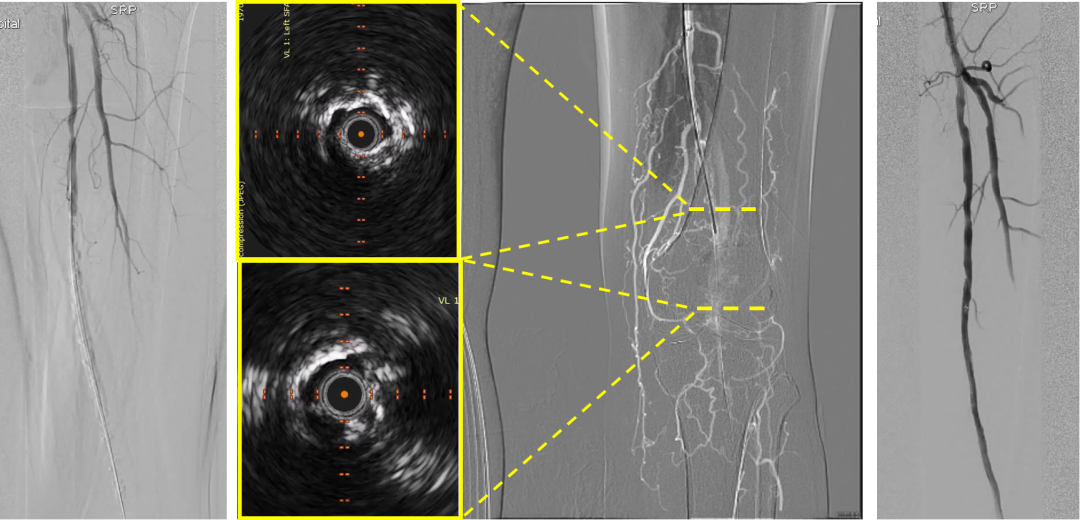

病例二:中度钙化--刻痕球囊+补救性减容

患者为中重度(2-3级)钙化。先以刻痕球囊扩张,但术后血流显影不佳。IVUS显示管腔内钙化明显,遂启动补救性减容,使用Jetstream 2.4mm减容器械。减容后再次造影,管腔显影明显改善。